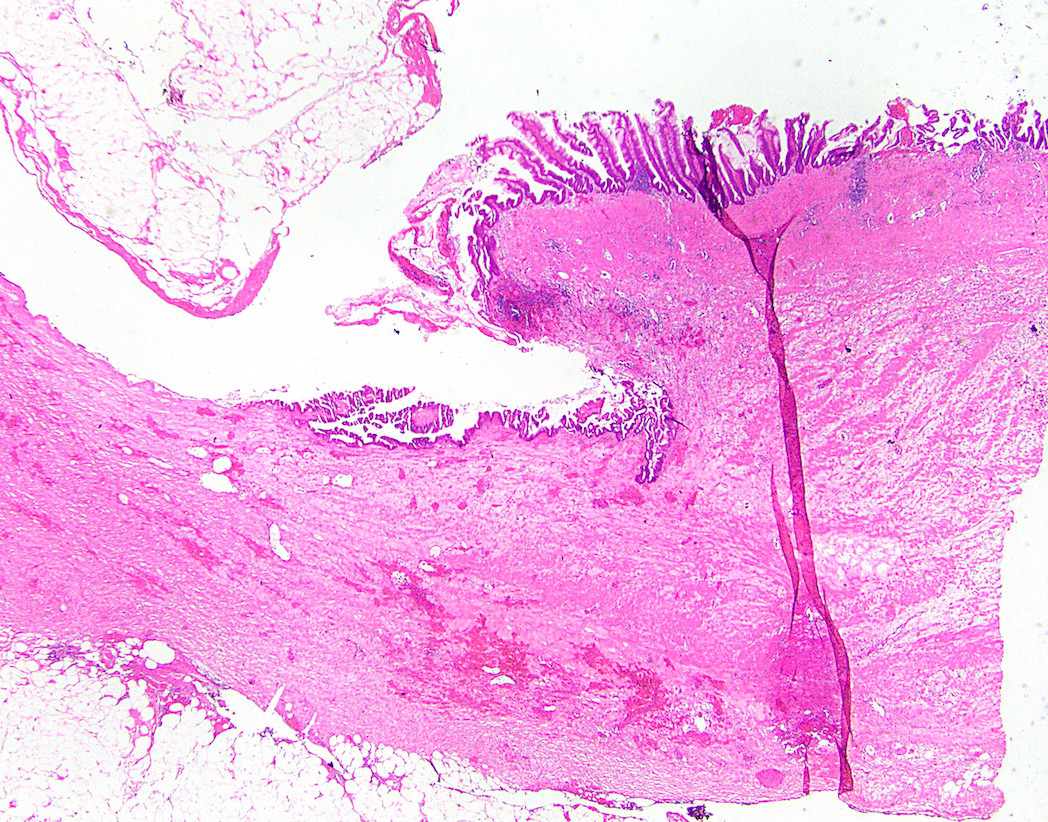

Microscopic (histologic) description

- Villous or occasionally flat proliferation of mucinous epithelial cells originating from appendiceal lumen

- Lesional cells typically demonstrate abundant apical mucin with elongated nuclei and low grade nuclear atypia (LAMN); however, nuclei may appear compressed or rarely high grade (HAMN)

- HAMN may show convoluted architecture, including micropapillary or cribriform features (Histopathology 2020;76:461)

- Often associated with atrophy of underlying lymphoid tissue, crypt loss and effacement of muscularis mucosae

- Broad dissection of mucin, epithelium or both may occur with potential involvement of extra-appendiceal surface, an important finding affecting prognosis

- Extra-appendiceal mucin incites a serosal reaction and may contain neovascularization, assisting in differentiation from benign transfer of mucin during gross examination

Microscopic (histologic) images

Contributed by Raul S. Gonzalez, M.D. and Michael Feely, D.O.